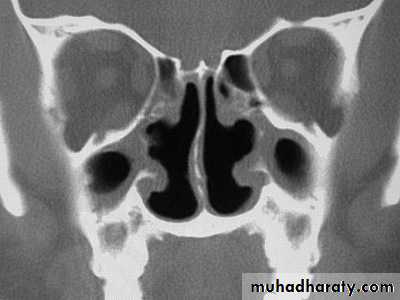

Degeneration of the ciliated epithelium and seromucinous glands causes the formation of thick adherent crusts in the nose theses become secondarily infected with saprophytic organism the bony structures of the turbinate atrophy and the airway is widened . the sinuses may be small due to arrested pneumatization but are often normal there appear to be tendency to spontaneous recovery in later life in some cases

The conditions now seldom seen is bilateral and more common in female it appear about puberty1.foul stench not noticed by the patient who is anosmic

2.epistaxis may follow separation of the crust

3. sensation of obstruction despite the unduly wide airway